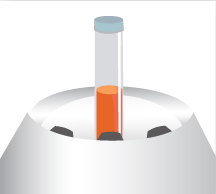

고성능 원심분리기를 통해

정제된 지방을 분리합니다